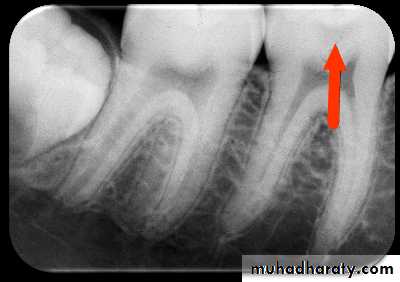

Recurrent Caries

Secondary or recurrent caries occurs adjacent to a pre-existing restoration. It is occurs in this region because ofInadequate cavity preparation

Defective margins

Incomplete removal of caries prior to the placement of restoration